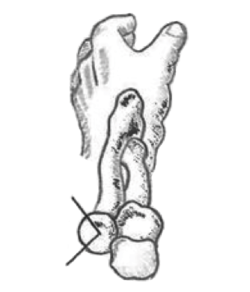

Se solicitarán radiografías simples (Rx) anteroposterior (AP) y lateral. También pueden ayudar las proyecciones oblicuas. En fracturas de la cabeza del radio no desplazadas podemos ver un signo indirecto de hemartros en el perfil estricto, la distensión de las almohadillas grasas anterior y posterior o “signo de la vela” (Figura 1). En casos de inestabilidad asociada podremos ver subluxación de la cabeza del radio respecto al cóndilo humeral. Si hay sospecha de lesión de la membrana interósea solicitaremos Rx posteroanteriores (PA) de ambas muñecas (en posición neutra) y podremos ver variaciones a nivel cubital distal.

Figura 1. Signo de la vela: distensión de las almohadillas grasas anterior y posterior por el hemartros.